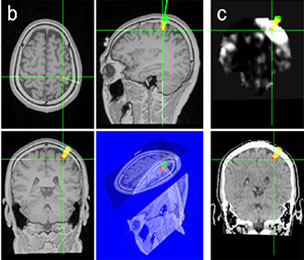

NeuroVisio(뉴로비지오)는 보이지 않는 뇌의 내부와 집중 초음파를 시각화시키는 브레인 이미지 네비게이터 플랫폼(Brain Image Navigator Platform)이다. 뇌의 MRI-CT촬영이미지를 3D로 시각화하며 뇌의 특정부위를 정밀하게 잡을 수 있다.

NeuroTrac(뉴로트랙)은 고정밀 3D 추적(Tracking)기술을 사용하여 실제공간과 영상공간을 정합하는 시스템이다. 환자가 움직여도 정확하게 시술 부위에 FUS를 정합할 수 있다.